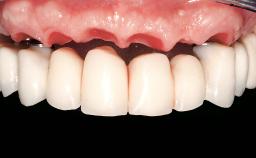

Conventional Loading of Eight Implants in the Maxilla and Final Restoration with a Full-Arch Gold-Ceramic FDP

A 35-year-old Caucasian female presenting with advanced periodontal disease involving both the maxillary and the mandibular dentition was referred for evaluation. The patient, a non-smoker in good general health, requested treatment for recurrent periodontal abscesses, tooth mobility, and discomfort during chewing, as well as restoration of her missing teeth with a fixed prosthesis to improve mastication and esthetics. All residual maxillary teeth exhibited plaque deposits, deep pockets, bleeding on probing, and class III mobility and were evaluated as hopeless. All residual mandibular teeth except tooth 37 could be maintained after periodontal therapy.

Prosthesis Type FDP